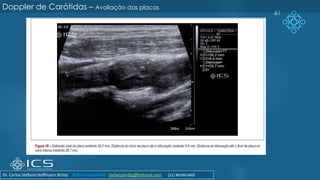

61

Doppler de Carótidas – Avaliação das placas

Dr. Carlos Stéfano Hoffmann Britto @drcarlosstefano stefanobritto@hotmail.com (31) 98799-0405

Caracterização da placa

QUANTO A:

➢ Ecogenicidade :

➢ Textura

➢ Superfície:

COMO DESCREVER:

➢ Hipoecogênica:

➢ adiposa;

➢ fibroadiposa

➢ Hiperecogênica:

➢ fibrosa;

➢ calcificada

➢ Homogênea: lipídica

➢ Heterogênea: fibrose, calcifação

➢ Regular (lisa): menor risco

➢ Irregular: maior risco (evitar o termo

ulcerada!)